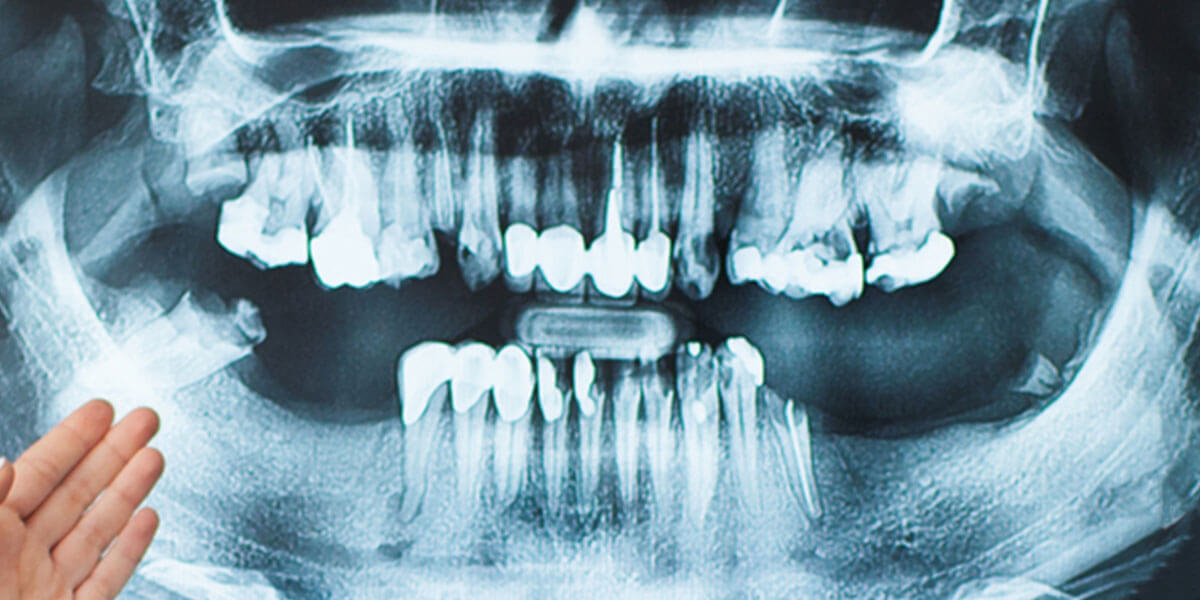

This procedure is used to regenerate lost bone around existing teeth, or in an area where teeth have been extracted. This procedure is often performed to protect existing teeth and the tissues that keep them in place from bacterial plaque. Where bone is lost or teeth have been extracted, there may be pockets where bacteria could collect and cause damage to the existing bone and tooth structures. If there are areas of concern, the gingival tissue can be folded back to allow removal of the disease-causing bacteria and placement of membranes, bone grafts, or tissue-stimulating proteins that can encourage the body’s natural ability to regenerate bone and tissue.